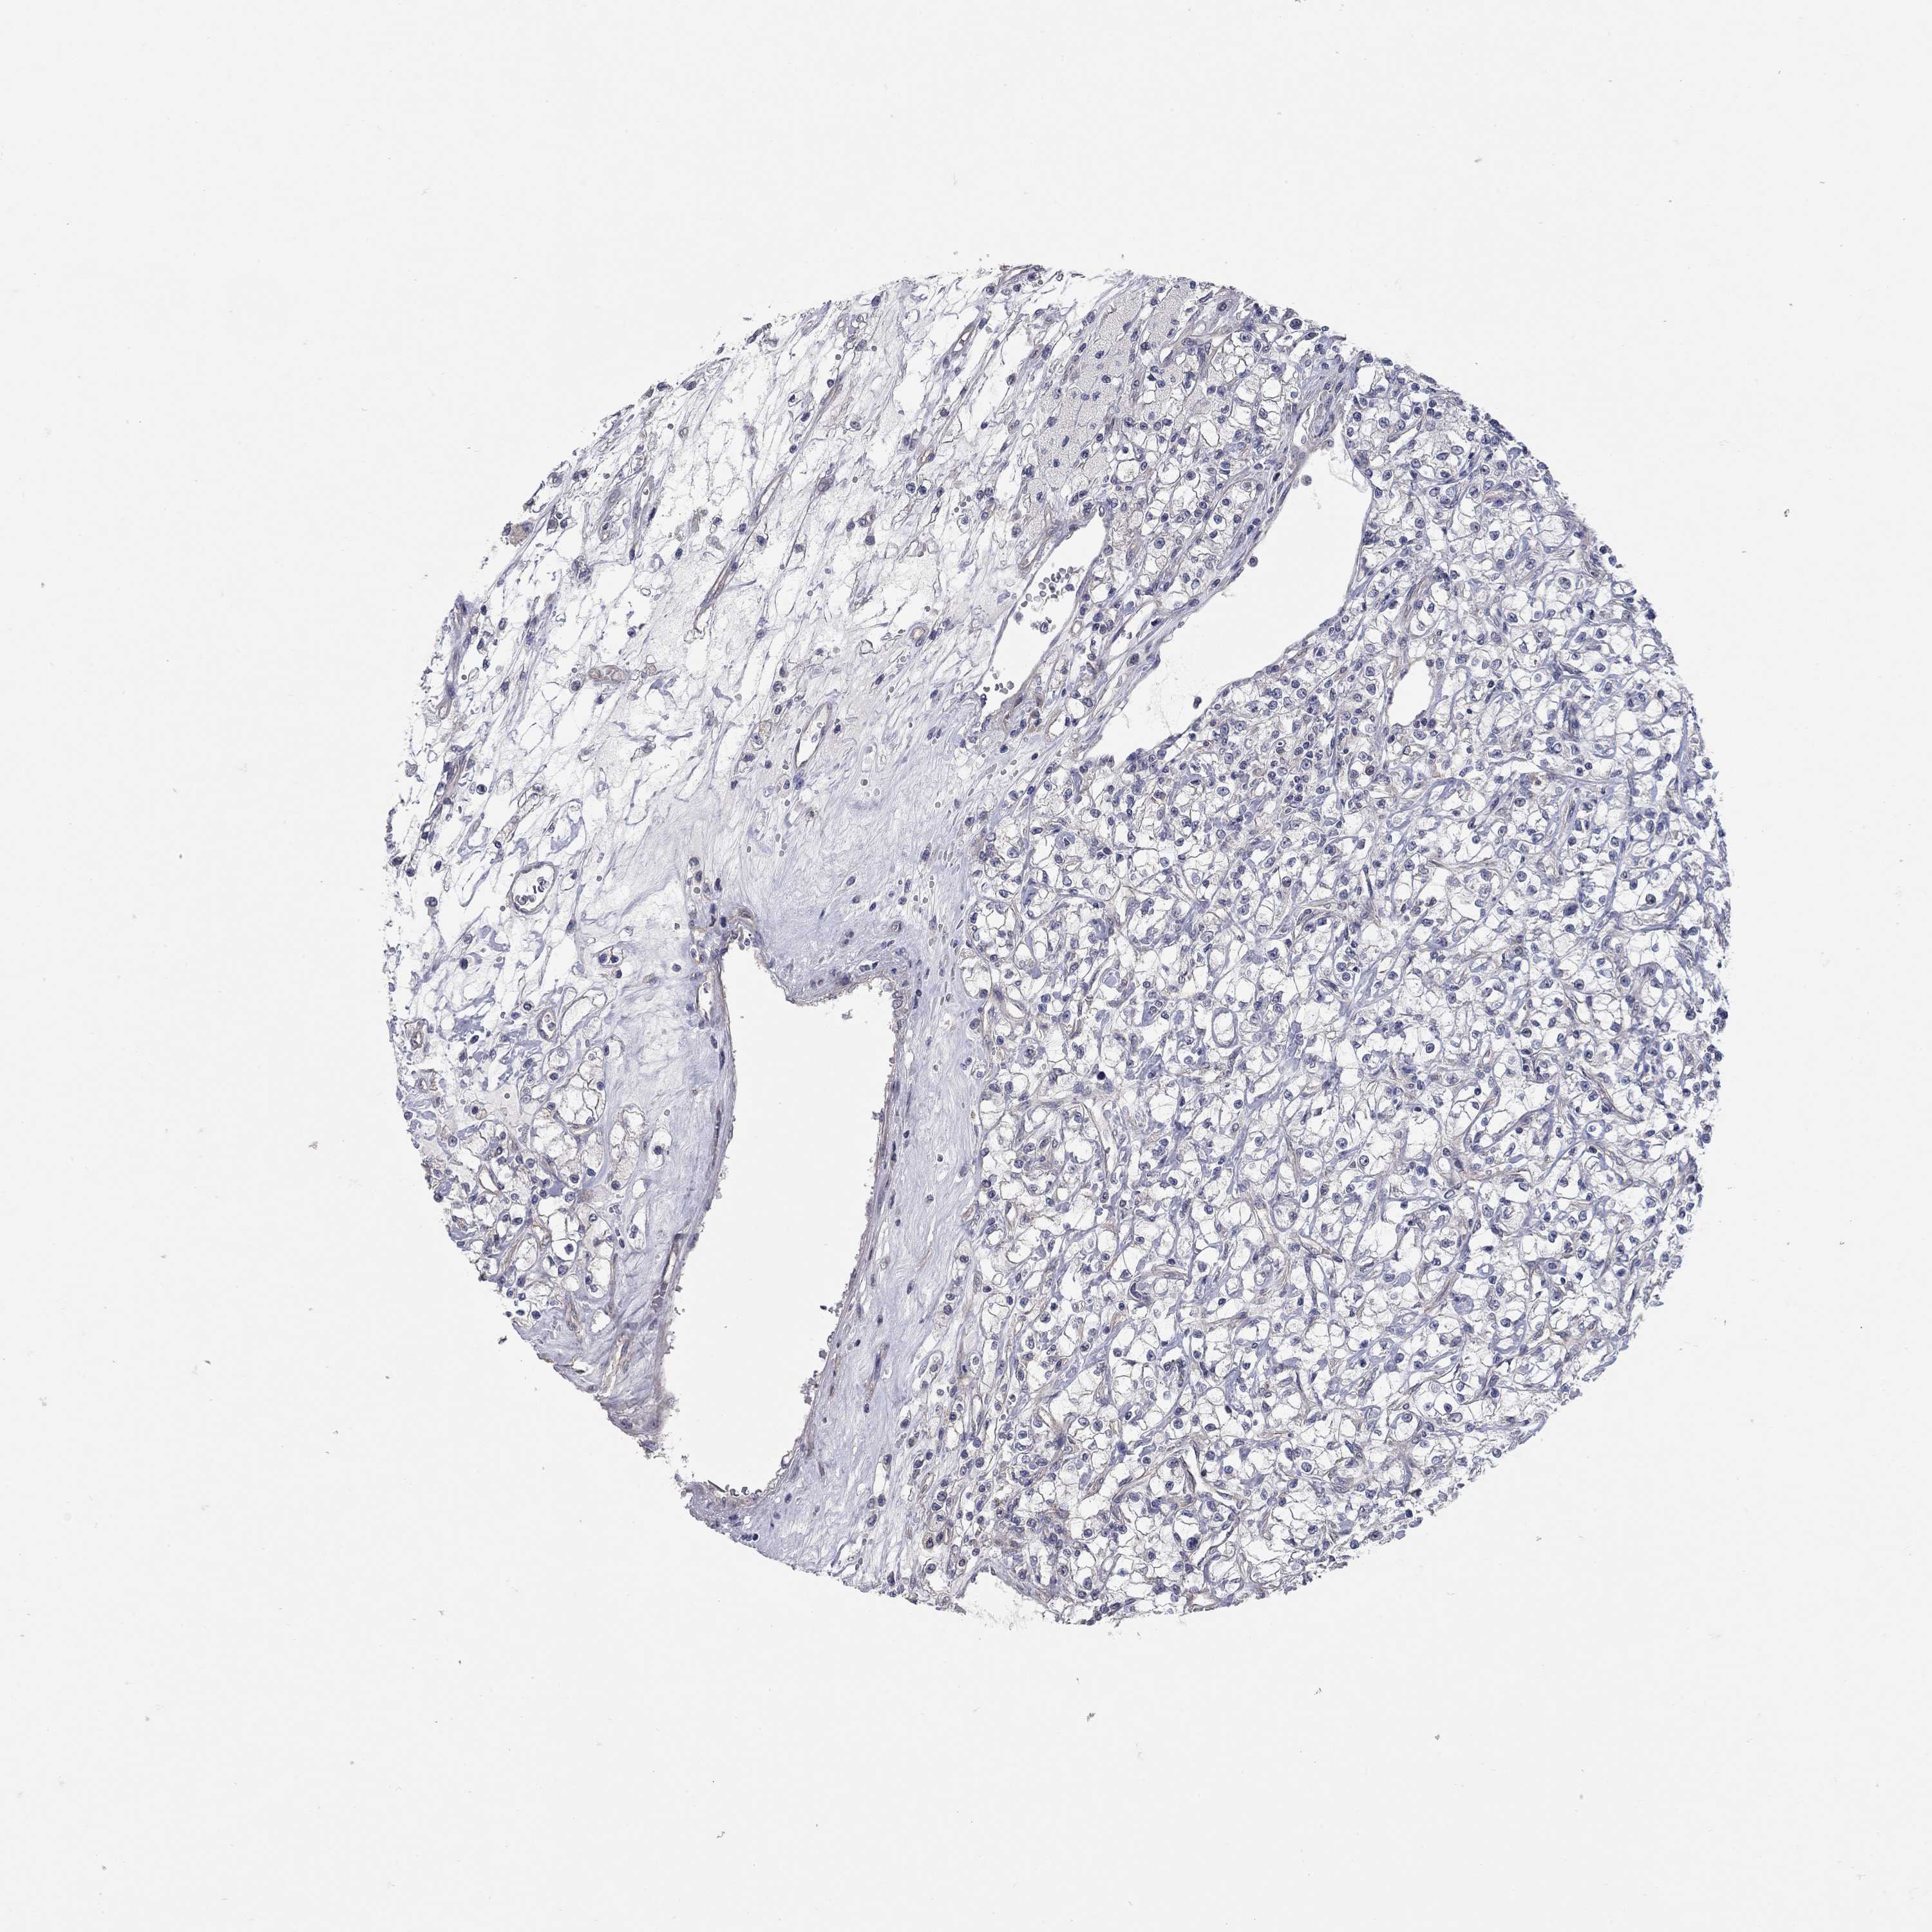

KIDNEY RENAL CLEAR CELL CARCINOMA (VALIDATION) - Interactive survival scatter ploti

The Survival Scatter plot shows the clinical status (i.e. dead or alive) for all individuals in the patient cohort, based on the same data that underlies the corresponding Kaplan-Meier plots. Patients that are alive at last time for follow-up are shown in blue and patients who have died during the study are shown in red.

The x-axis shows the expression levels (FPKM) of the investigated gene in the tumor tissue at the time of diagnosis. The y-axis shows the follow-up time after diagnosis (years). Both axes are complimented with kernel density curves demonstrating the data density over the axes. The top density plot shows the expression levels (FPKM) distribution among dead (red) and alive patients (blue). The right density plot shows the data density of the survived years of dead patients with high and low expression levels respectively, stratified using the cutoff indicated by the vertical dashed line through the Survival Scatter plot. This cutoff is automatically defined based on the FPKM cutoff that minimizes the p-score. The cutoff can be changed by dragging the vertical line or by entering a cutoff value in the square labeled "Current cut-off".

Under the Survival Scatter plot the p-score landscape (black curve; left axis) is shown together with dead median separation (red curve; right axis). Dead median separation is the difference in median mRNA expression between patients who have died with high and low expression, respectively. It is calculated as follows: median FPKM expression of dead patients with high expression - median FPKM expression of dead patients with low expression. This is intended to aid the user in visually exploring custom cutoffs and the associated p-scores and dead median separation.

Individual patient data is displayed and can be filtered by clicking on one or more of the category buttons on the top of the page. Categories describing expression level and patient information include: high, low, alive, dead, female, male and tumor stages. The scale of the x-axis can be toggled between linear and log-scale by clicking on the "x log" button. Mouse-over function shows TCGA ID, patient information and mRNA expression (FPKM) for each patient.

& Survival analysisi

Kaplan-Meier plots summarize results from analysis of correlation between mRNA expression level and patient survival. Patients were divided based on level of expression into one of the two groups "low" (under cut off) or "high" (over cut off). X-axis shows time for survival (years) and y-axis shows the probability of survival, where 1.0 corresponds to 100 percent.

WASF3 is not prognostic in Kidney Renal Clear Cell Carcinoma (validation)

Best expression cut offi

Based on the FPKM value of each gene, patients were classified into two groups and association between prognosis (survival) and gene expression (FPKM) was examined. The best expression cut-off refers the FPKM value that yields maximal difference with regard to survival between the two groups at the lowest log-rank P-value. Best expression cut-off was selected based on survival analysis .

When clicking on this number, the vertical dashed line indicating cut-off, the interactive survival plot, and the Kaplan-Meier curve will be adjusted to show results based on the best expression cut-off.

: 2.35

P scorei

Log-rank P value for Kaplan-Meier plot showing results from analysis of correlation between mRNA expression level and patient survival.

N/A

TCGA RNA samplesi

RNA-seq data is reported as average FPKM (number Fragments Per Kilobase of exon per Million reads), generated by the The Cancer Genome Atlas (TCGA) .

Normal distribution across the dataset is visualized with box plots, shown as median and 25th and 75th percentiles. Points are displayed as outliers if they are above or below 1.5 times the interquartile range. FPKM values of the individual samples are presented next to the box plot.

Average pTPM 3.0

Number of samples 100